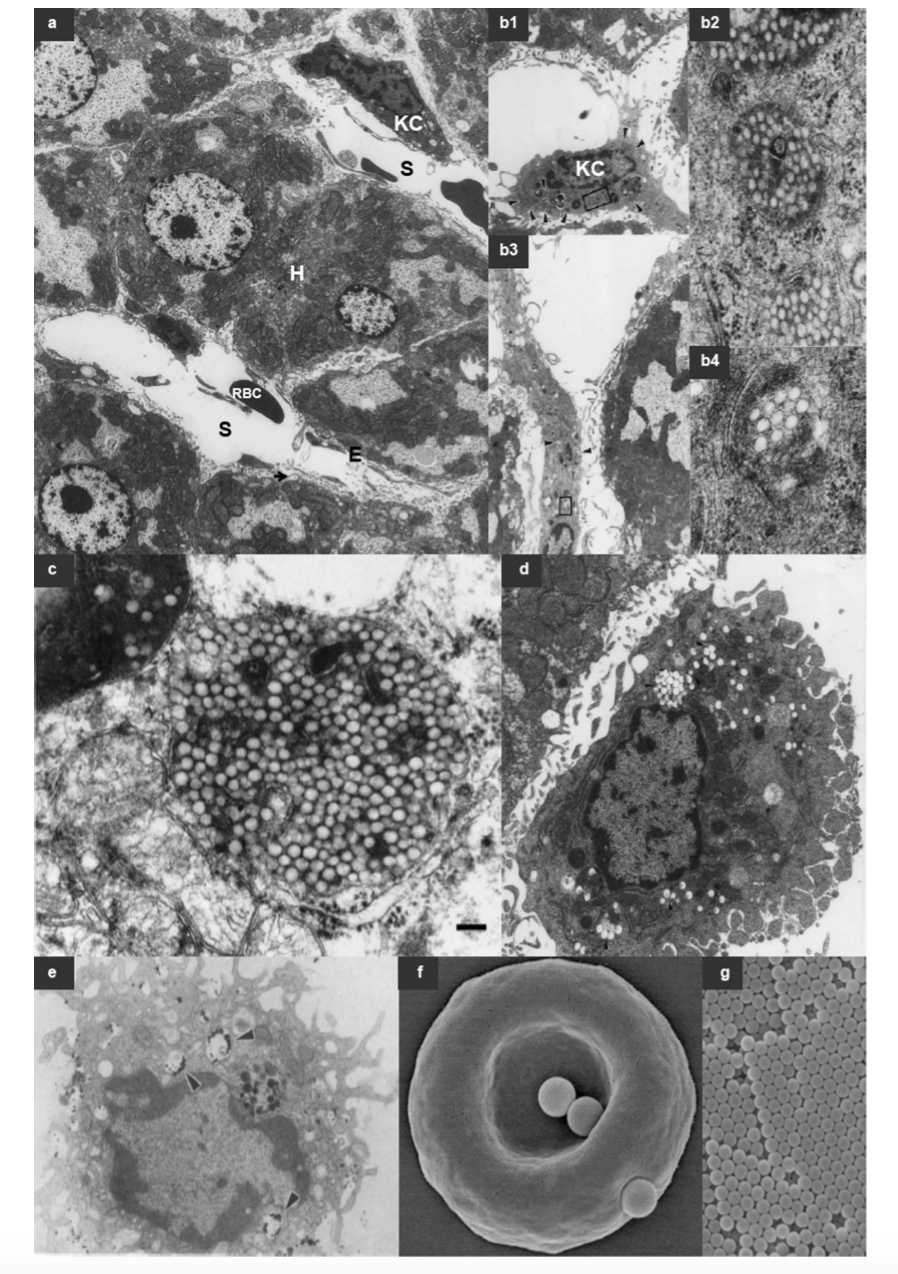

- Characterization and Analysis: Utilizing various techniques (such as dynamic light scattering and transmission electron microscopy) to analyze the physicochemical properties of liposomes, assessing parameters like particle size, morphology, and drug encapsulation efficiency.

Fig.1 The Long Circulating Nanoparticles.1,3